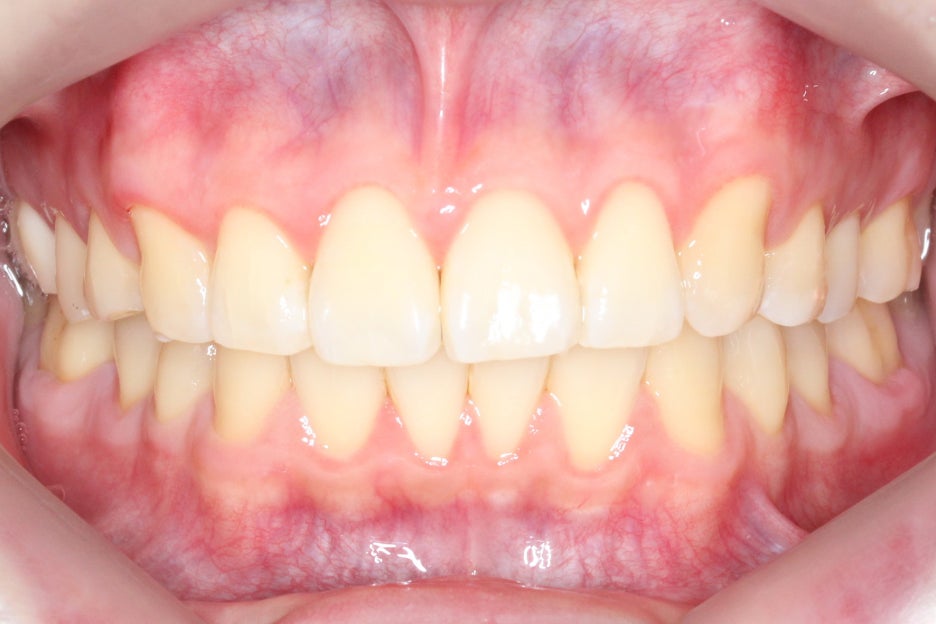

정면에서 본 구내사진을 보면

교정 전과 달리 전치부의 crowding이 사라지고

가지런하게 바뀐 치열을 확인할 수 있는데요,

좌측으로 심하게 기울어져 있던

치아의 정중선 또한 윗니부분교정 후

중앙으로 잘 맞춰진 모습입니다.